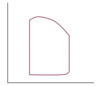

Click on the region of the alveolar compliance curve where ventilation is the greatest.

Alveolar ventilation is a function of alveolar size and its position on its compliance curve (Alveolar compliance = Alveolar volume / Alveolar Pressure).

The best ventilated alveoli are the most compliant.

They exchange more gas, because their volumes change more throughout the respiratory cycle.

These alveoli reside at the steep slope of the curve.

The least ventilated alveoli are the least compliant.

They exchange less gas, because their volumes change very little throughout the respiratory cycle.

These alveoli reside near the top of the curve.

A patient is scheduled for a VATS with lung resection. Click on the alveolar compliance curve that BEST illustrates what happens after he is anesthetized and placed in the lateral decubitus position.

When the anesthetized patient is placed in the lateral decubitus position:

The nondependent lung moves from the flat (noncompliant) region of the curve to an area of better compliance. Ventilation is best here, because the lung is on a favorable position of the curve.

The dependent lung moves from the slope (highly compliant) to the lower, flatter area of the curve. In this region, the reduction of alveolar volume contributes to atelectasis. Perfusion is best here due to gravity.

The net effect is that ventilation is better in the nondependent lung and perfusion is better in the dependent lung. This creates V/Q mismatch.